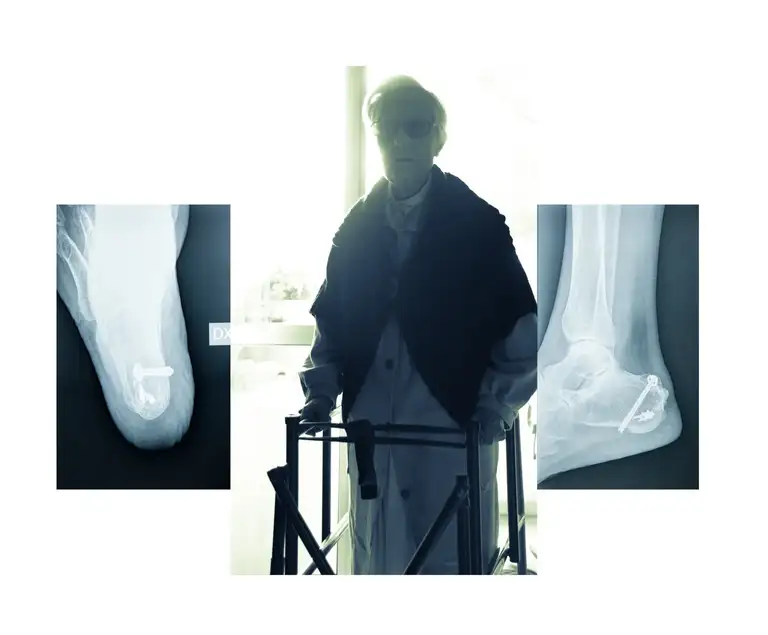

L’incipit del lavoro è costituito dall’immagine radiografica del teschio, la cui osservazione ha consentito allo sguardo di creare una relazione mutevole tra gli spazi, avvalendosi degli elementi luce/buio e trasparenza/opacità. L’alternarsi della contemplazione del pieno e del vuoto, del luminoso e dell’oscuro ha generato una riflessione su dentro e fuori, su involucro e contenuto, in ultima analisi su vita e morte.

La messa in quadro del teschio e del volto ha implicato la creazione e l’utilizzo di una sottile linea di demarcazione che nell’atto di separare i due elementi li ha ulteriormente posti in relazione. Si è così venuta a creare casualmente – o forse causalmente – una relazione spaziale ortogonale tra gli oggetti, traducibile in un simbolo, nell’immagine frammentata di qualcosa che indugiava a manifestarsi: la porzione di una croce.

La croce è divenuta da quel momento idea dominante dello sguardo e prepotentemente anche soggetto del racconto fotografico. Laddove vita e morte instaurano un dialogo così intenso e serrato, essendo l’una ragione dell’altra, la croce diviene necessariamente figura di entrambe e dunque anche di tutti gli ingredienti di cui si compone l’esistenza: il piacere e la sua negazione, il riposo, l’attesa, la fuga, l’espiazione, la perdita ed il guadagno, la ripresa.

L’epifania conclusiva di una croce inesistente, materializzatasi allo sguardo in virtù di un gioco di ombre stagliate sulla superficie di una struttura insolita, ha richiamato inevitabilmente alla mente il Golgota, il luogo della croce per eccellenza, ma anche e soprattutto, in quello che è il suo più stretto senso etimologico, il luogo del teschio. Si è così chiuso il cerchio: dal teschio alla croce e dalla croce nuovamente al teschio, in una danza che ha per protagonisti eros e thanatos in un inquietante gioco di scatole cinesi.